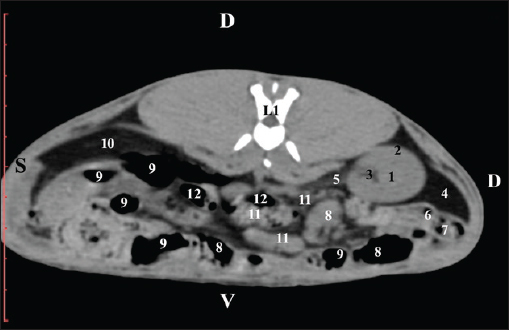

Fig. 3. Pre-contrast computed tomography (CT) anatomical scan of regio abdominis cranialis at the L1 level. (1) Medulla renis; (2) cortex renis; (3) pelvis renalis; (4) lobus caudatus (proc. caudatus) with visceral adipose tissue; (5) ureter; (6) pars descendens of the duodenum; (7) jejunum; (8) cecum; (9) colon ascendens; (10) lien; (11) colon descendens; (12) colon transversum. At the L2 level, the right kidney was in contact with the liver’s proc. caudatus, pars descendens of the duodenum, and the ileum. Pelvis renalis was a distinct hypoattenuated funnel-shaped soft tissue finding, whose narrow end pointed at the renal hilum and passed into the ureter. Recessus renalis was a clearly visible hypoattenuated widening of the central part of the renal pelvis in the dorsal and ventral directions (Figs. 4 and 5).

Fig. 4. Pre-contrast CT anatomical scan of the regio-abdominis media at the cranial L2 edge level. (1) Ren dexter; (2) pelvis renalis; (3) lobus caudatus (proc. caudatus) with visceral adipose tissue; (4) pars descendens of the duodenum; (5) ileum; (6) jejunum; (7) colon ascendens; (8) cecum; (9) colon transversum; (10) colon descendens; (11) lien; (12) pars transversa of the duodenum ; (*) ureter; (white arrow) recessus renalis.

Fig. 5. Pre-contrast computed tomography (CT) anatomical scan of the regio-abdominis media at the caudal L2 edge level. (1) Ren dexter; (2) pelvis renalis; (3) lobus caudatus (proc. caudatus) with visceral adipose tissue; (4) gl. adrenalis dextra; (5) ileum; (6) jejunum; (7) colon ascendens; (8) cecum; (9) colon transversum; (10) colon descendens; (11) lien; (*) ureter; (white arrow) recessus renalis. At the L3 level, the anatomical adjacencies of the right kidney with the pars descendens of the duodenum, ileum, cecum, and colon descendens were visualized. Hypoattenuated right ureter and normoattenuated gl. adrenalis dextra were situated medially to the right kidney. Extremitas caudalis of the right kidney was a clearly visible normoattenuated finding, surrounded by hypoattenuated borders of abdominal adipose collections (Figs. 6 and 7).